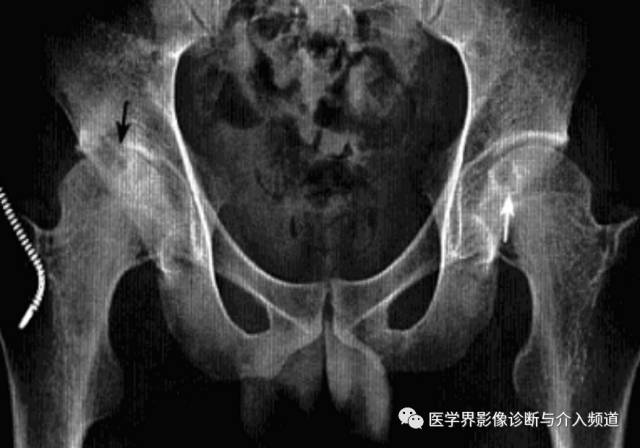

1、平片:双侧对称受累,早期骨质疏松,关节囊膨隆,股骨头及髋臼骨质侵蚀糜烂;中期关节间隙一致性狭窄,软骨下囊性变,关节面边缘骨质增生,坐骨结节、坐骨耻骨支及股骨大转子可伴骨膜炎;晚期股骨头内移、髋臼内突,关节腔闭锁呈骨性强直。

2、CT:早期少量关节腔积液,可伴髂腰肌囊扩张,同时股骨头骨质疏松,股骨头及髋臼缘囊状、虫蚀状骨质缺损;中期关节面边缘硬化、囊变、骨赘形成,股骨头基底滑膜附着处增生,髋关节间隙均匀一致性狭窄消失,双侧髋对称性骨性强直,股骨头及髋臼可普遍性肥大。